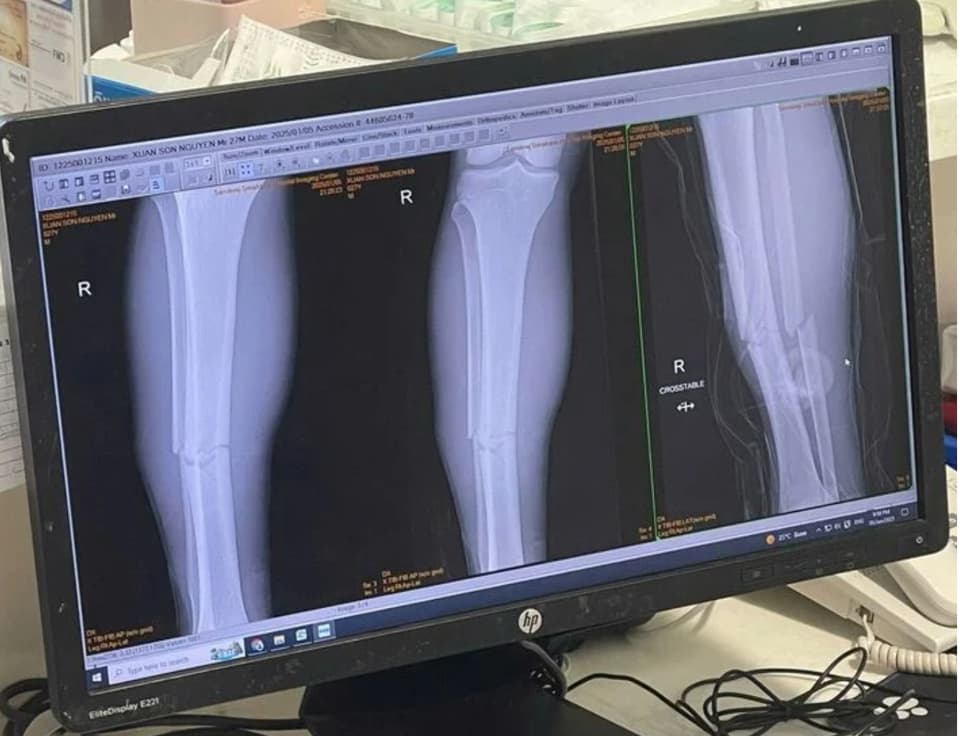

Xuân Son chấn thương rồi

Thương Xuân Son quá, e đã cống hiến hết mình vì đất nước & bóng đá VN. Đêm vui này thật k trọn vẹn vì sự thiệt thòi quá lớn của e.

Ảnh chụp X quang xương chân phải Xuân Son.